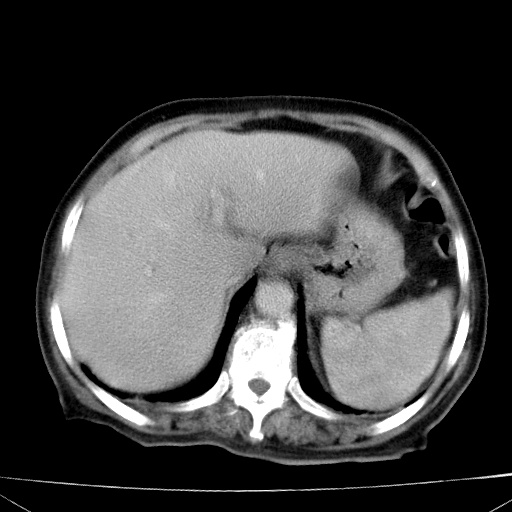

网站人气太旺!昨天的帖子就沉到海底,只好再发贴!ct18338:女 78岁,肝胆病变,已增强,再会诊!原帖链接:http://www.radida.com/bbs/forum.php?mod=viewthread&tid=50032

1)考虑胆囊癌侵犯肝脏并肝门区、腹膜后及右侧膈角后淋巴结转移。2)肝左叶近肝顶部囊肿。3)肝左叶肝内胆管结石。4)左肾近下极囊肿。